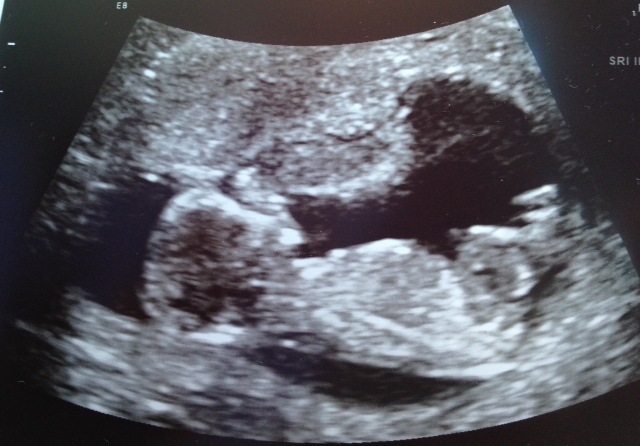

13 weeksAttachment 9940

Looks like a boy to me :)

looks boy

Ever so slight pink lean.

I am thinking blue!